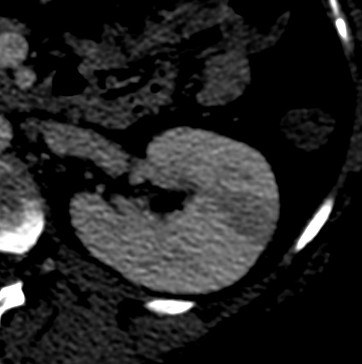

Se procede a realizar TC abdomino-pélvico con contraste en fase nefrográfica y excretora:

Conclusión: se nos presentó un caso de un paciente con una sospecha de infección renal complicada ya que tras cuatro días de tratamiento antibiótico no hubo mejoría. Ante los hallazgos observados en TC, podemos establecer el diagnóstico de pieloureteritis renal izquierda con signos de hidroureteronefrosis leve hasta vejiga.

C- UIV de una hidroureteronefrosis izquierda leve (grado II/IV) hasta vejiga.

- Protocolo: TC abominopélvico sin y con contraste en fase nefrográfica (70 seg) +/- fase tardía ( a los 7 – 10 min) solo si se sospecha obstrucción.

- TC con contraste: Las áreas afectadas del parénquima aparecen como zonas con baja atenuación debido al edema. Las áreas hiperdensas son menos frecuentes y corresponden a focos de hemorragia. Estos hallazgos son mejor valorables a través de la aplicación de contraste, ya que un TC en vacío pueden pasar desaprecibidas.